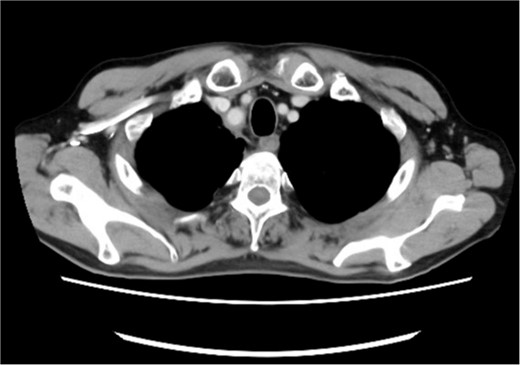

A 72-year-old man diagnosed with NSCLC was referred for possible surgical treatment of a solitary nodule detected in the mesorectum. His medical history included hypertension and endoscopic resection of colonic polyps, with no prior thromboembolism. He had received combined medical treatment for NSCLC (cT4N0M0, stage IIIA) (Fig. 1), including four courses of cisplatin and docetaxel chemotherapy with a 60 Gy/30 fractions radiation dose, followed by 1 year of consolidation therapy with durvalumab (640 mg/body). The patient tolerated the treatment well, achieving a complete response 13 months before presentation (Fig. 2). However, the mesorectal nodule was incidentally discovered during surveillance CT after NSCLC treatment completion. It was round, 15 mm in diameter, showed contrast enhancement, and was near the mesorectal vessels (Fig. 3a and b). An FDG PET/CT scan revealed a solitary mesorectal nodule with an SUVmax of 10.3 (Fig. 4). Consequently, the radiologist suggested differential diagnoses of malignant lymphoma and metastatic lymph nodes from the urinary or lower gastrointestinal tract, as NSCLC typically does not metastasize to mesorectal lymph nodes. No other abnormal FDG uptake was observed. Laboratory tests showed normal levels for tumor markers, including carcinoembryonic antigen, sialyl Lewis X (SLX), squamous cell carcinoma antigen, neuron-specific enolase, cytokeratin fragment (CYFRA), progastrin-releasing peptide, and blood coagulability was within the normal range. Total colonoscopy revealed no neoplastic lesions, and urinary cytology showed nonmalignant urothelial cells. Noninvasive diagnostic approaches, including endoscopic or CT-guided biopsy, were extensively discussed but deemed difficult because of anatomical restrictions, risk of dissemination, and procedure-related complications (such as bleeding or perforation). Because of the potential malignancy and need for en-bloc resection, we opted for surgical resection using a standardized laparoscopically assisted mesorectal excision technique. During rectal dissection, the nodule was not visible through the posterior and lateral sides because it was completely embedded in the mesorectum. Therefore, a Pfannenstiel incision was made in the lower abdomen to exteriorize the rectum after the division of the proximal colon. The nodule was confirmed by direct palpation, marked with a stitch, and subsequently removed after intracorporeal transection of the distal rectum. We inspected the resected specimen and confirmed that the nodule was incorporated (Fig. 5a and b). A colorectal anastomosis was then performed using a double-stapling technique with a circular stapler. The postoperative course was uneventful, except for a slight elevation of the d-dimer level (up to 3.26 μg/ml) on postoperative Day 7, which normalized spontaneously without intensive anticoagulation therapy. The patient was discharged on postoperative Day 10. Pathological examination revealed that the 7-mm white nodule was an intravenous organized thrombus in the mesorectum surrounded by granulation tissue, with no malignancy observed (Fig. 6a and b). Postoperatively, the patient did not require additional chemotherapy or anticoagulation therapy. During the 16-month follow-up, no radiological evidence of NSCLC recurrence and thromboembolism was detected (Fig. 7).

Posttreatment computed tomography (CT) image. No apparent tumorous lesions were identified.